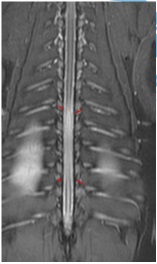

I’ve recently been working with a canine client, Willow, who has been experiencing loss of strength and sensitivity in her hind legs. The vet diagnosed a lesion, within her spinal canal but outside of the spinal cord, causing compression at the T7 vertebra and resulting in weakness and loss of sensation.